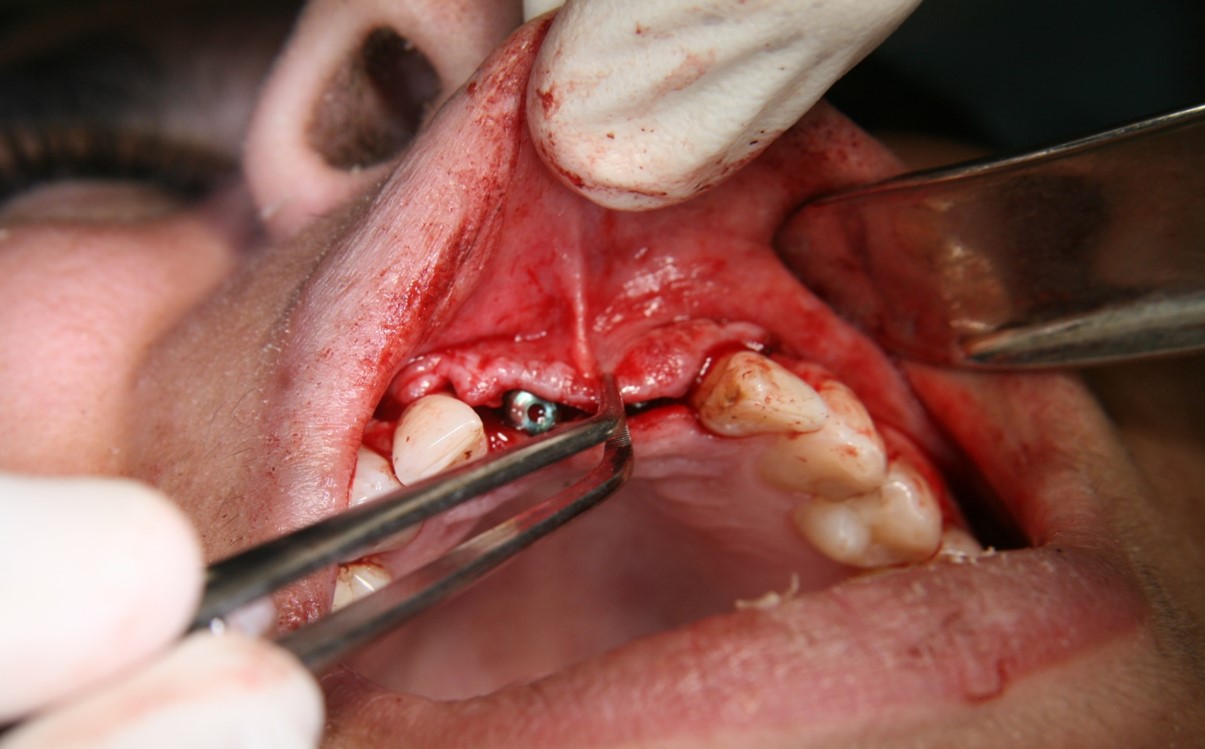

Fig 1. Tooth extraction resulted in a defected wall.

Figure 1

Fig 2. A PLGA alloplast bone grafting material was placed and molded to shape the area.

Figure 2